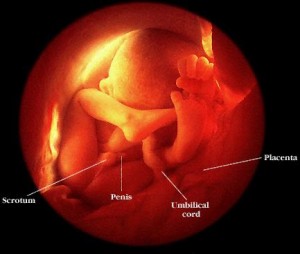

25 haftalık bebek Bebeğinizin boyu 30 cm oldu. İç kulağındaki kemiklerde sertleşmeye başladığından artık sizi daha iyi duyabiliyor. Aslında babasının sesini, sizin sesinizden daha net duyabiliyor. Eşinize söyleyin, karnınıza yaklaşıp bebeğinize “Merhaba” desin lütfen !

http://www.gulselim.com/wp-content/uploads/2009/05/25hafta.gif

bebek5-5f.gif